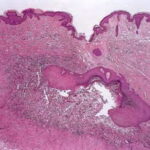

Foreign Body Reactions Foreign substances, when injected or implanted accidentally into the skin, can produce a nonallergic foreign-body reaction or, in persons specifically sensitized to them, an allergic response (. In addition, certain substances formed within the body may produce a nonallergic foreign-body reaction when deposited in the dermis or subcutis. Such endogenous foreign-body reactions are produced, for instance, by urates in gout and by keratinous material in pilomatricoma, as well as in ruptured epidermoid and trichilemmal cysts. |

Histopathology. A nonallergic foreign-body reaction typically shows a granulomatous response marked by histiocytes and giant cells surrounding foreign material. Often, some of the giant cells are of the foreign-body type, in which the nuclei are in haphazard array. In addition, lymphocytes are usually present, as may be plasma cells and neutrophils. Frequently, some of the foreign material is seen within macro phages and giant cells, a finding that of course is of great diagnostic value. The most common cause of a foreign-body granuloma is rupture of a hair follicle or follicular cyst, and sometimes only the cyst contents, rather than residual cyst wall, is identifiable . Exogenous substances producing nonallergic foreign-body reactions include silk and nylon sutures , wood or other plant material , paraffin and other oily substances, silicone gel, talc, surgical glove starch powder, and cactus spines. Some of these substances-nylon sutures, wood, talc, surgical glove starch powder, and sea urchin spines-are doubly refractile on polarizing examination. Double refraction often is very helpful in localizing foreign substances. Knife marks in the section may be an additional clue to the presence of particulate foreign matter |